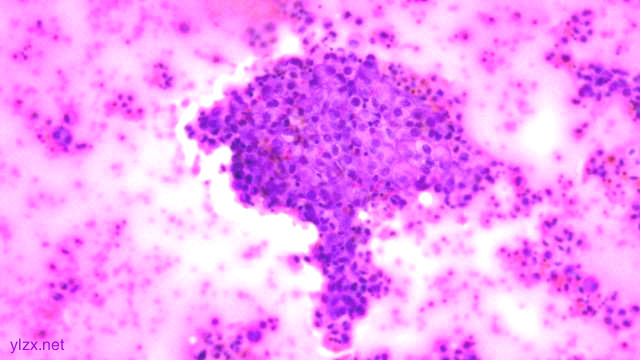

1.宫颈2点、10点:鳞状上皮下间质内见瘤组织弥漫增生,胞浆宽阔,红染,核小,较一致,部分细胞核偏位,部分细胞可见核仁;

2.宫颈5点:鳞状上皮下间质内见少量异型细胞巢,核增大,深染,浆红染,少量细胞浆内见黏液,印戒样;宫颈管搔刮组织:见血凝块、宫颈内膜组织,间质见异型细胞条索,形态同宫颈5点。

鳞状上皮下间质内见瘤组织弥漫增生,胞浆宽阔、红染,核小,较一致

瘤细胞排列偏稀疏,核小,深染,胞浆红

间质内见异型细胞巢,核增大,深染

间质内见异型细胞条索,核增大,深染,浆红

少量细胞浆内见黏液,印戒样

瘤细胞核偏位,浆红染

高倍瘤细胞见红色核仁